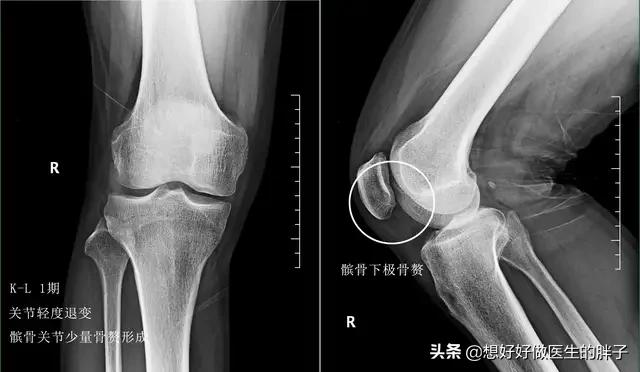

所以从理论上来讲,骨赘是属于帮助我们身体维持稳定性的一种结构,但是当关节软骨进一步的磨损,骨赘会越来越大,就会刺激到周边的软组织、韧带、神经等组织与结构,导致患者出现明显的疼痛,当检查x线的时候会发现这些骨赘形成类似刺状,于是骨刺这个说法就诞生了……!

大部分关节软骨损伤的患者在早期的症状不是特别的重,偶尔表现为上下楼梯的疼痛和屈伸关节的时候有明显的疼痛,此时很多患者去医院进行检查,会发现有轻度的骨质增生,这是由于关节软骨并不是磨损的特别重,所以骨赘不会形成的特别多,此时作为患者应该是以休息为主,减少刺激关节软骨的动作,尽量不要做剧烈的运动来反复刺激关节软骨;可以尝试口服氨糖三个月观察疗效;如果疼痛比较明显的时候可以外用一些抗炎镇痛药帮助控制疼痛;此时可以适当的进行关节周围肌肉力量的强化训练,帮助增加关节的稳定性,也就侧面的减缓了骨赘形成的速度,这种康复锻炼应该贯穿于整个骨赘治疗的全程,是基础治疗。